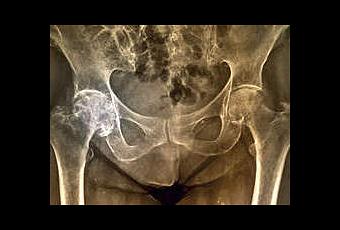

Après le scandale des prothèses mammaires fruduleuses, c’est peut-être le début d’une affaire de prothèses de hanches défectueuses.

Une enquête menée conjointement par le BMJ et la BBC révèle un risque d’intoxication métallique lié à certaines prothèses de hanche, remettant une nouvelle fois en cause la sécurité des dispositifs médicaux.

Après les prothèses PIP, les prothèses de hanches ASR risque de causer du souci aux autorité sanitaires. «Plusieurs centaines de milliers de personnes dans le monde pourraient avoir été exposées à des taux dangereusement élevés de métaux toxiques via des prothèse de hanche défectueuse », alertent en effet le BMJ et la BBC dans un communiqué publié mardi.

Selon le BMJ, ces risques seraient connus et documentés depuis plusieurs décennies, mais auraient été passés sous silence par certains fabricants et mal appréhendés par les autorités sanitaires concernées. Les auteurs dénoncent notamment l’attentisme observé vis à vis des prothèses ASR, commercialisées entre 2003 et 2010 par DePuy Orthopaedics. Ces modèles ont la particularité d’associer un couple métal sur métal, un dispositif réputé plus résistant que les autres associations à base de céramique, mais qui a l’inconvénient, du fait des frottements, de libérer des ions métalliques.